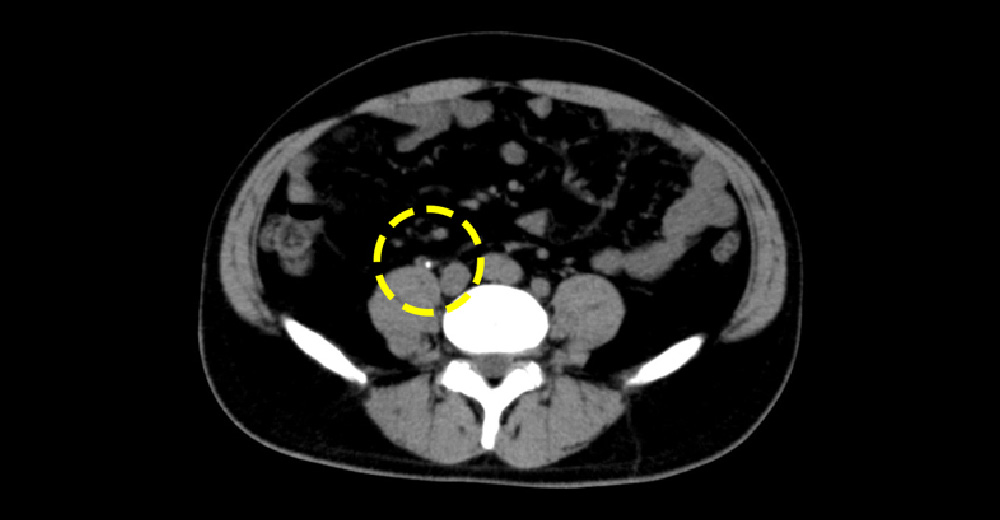

急性虫垂炎

腹痛と血尿を訴えて受診。

虫垂が破れて、周囲に うみ をためています。炎症の波及で、膀胱へ波及→血尿が出ていました。